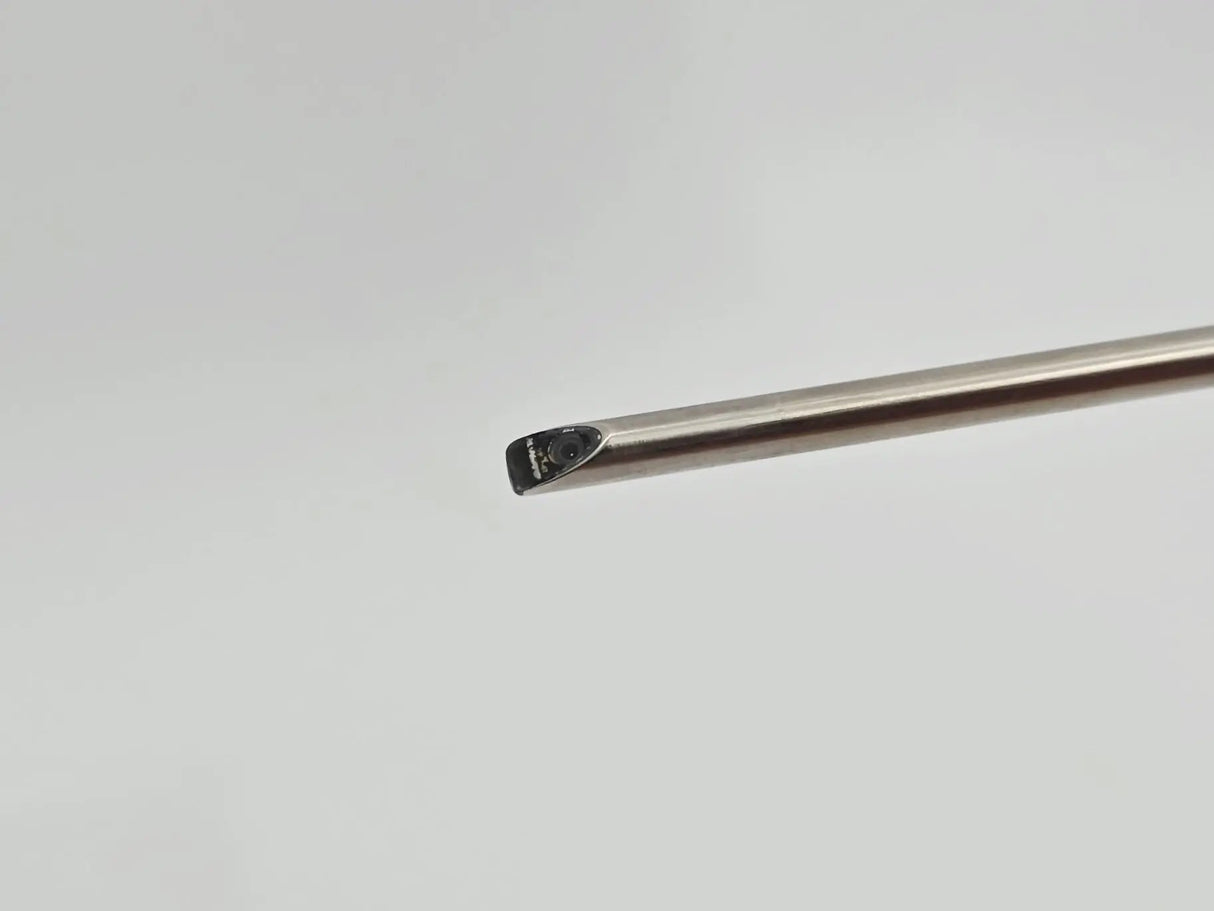

ConMed Linvatec HD4700 4.0 mm 70° HD Arthroscope w/ Case Autoclavable 9-1/4"

ConMed Linvatec HD4700 4.0 mm 70° HD Arthroscope w/ Case Autoclavable 9-1/4"

• Model: HD4700

• 4.0mm

• 70-Degree

• Autoclavable

• Overall Length: 9-1/4 inches

The ConMed Linvatec HD4700 4.0 mm 70° HD Arthroscope is a high-definition endoscopic instrument designed for precision visualization during orthopedic arthroscopy procedures. With a 4.0 mm diameter and a 70° field of view, it offers a wide-angle perspective, allowing surgeons to navigate and assess joint structures effectively. The 170 mm working length provides optimal reach within the joint space, facilitating comprehensive examination and intervention.

Crafted from high-strength medical-grade stainless steel, the HD4700 arthroscope ensures durability and resistance to wear, making it suitable for repeated use in surgical settings. The inclusion of a sapphire lens enhances image clarity and scratch resistance, contributing to long-term optical performance. Its autoclavable design allows for efficient sterilization, reducing turnaround time between procedures and supporting cost-effective surgical workflows.